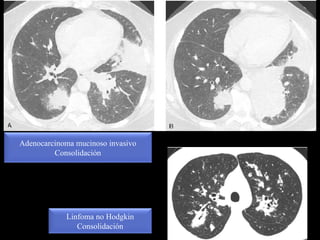

Adenocarcinoma mucinoso invasivo

Consolidación

Linfoma no Hodgkin